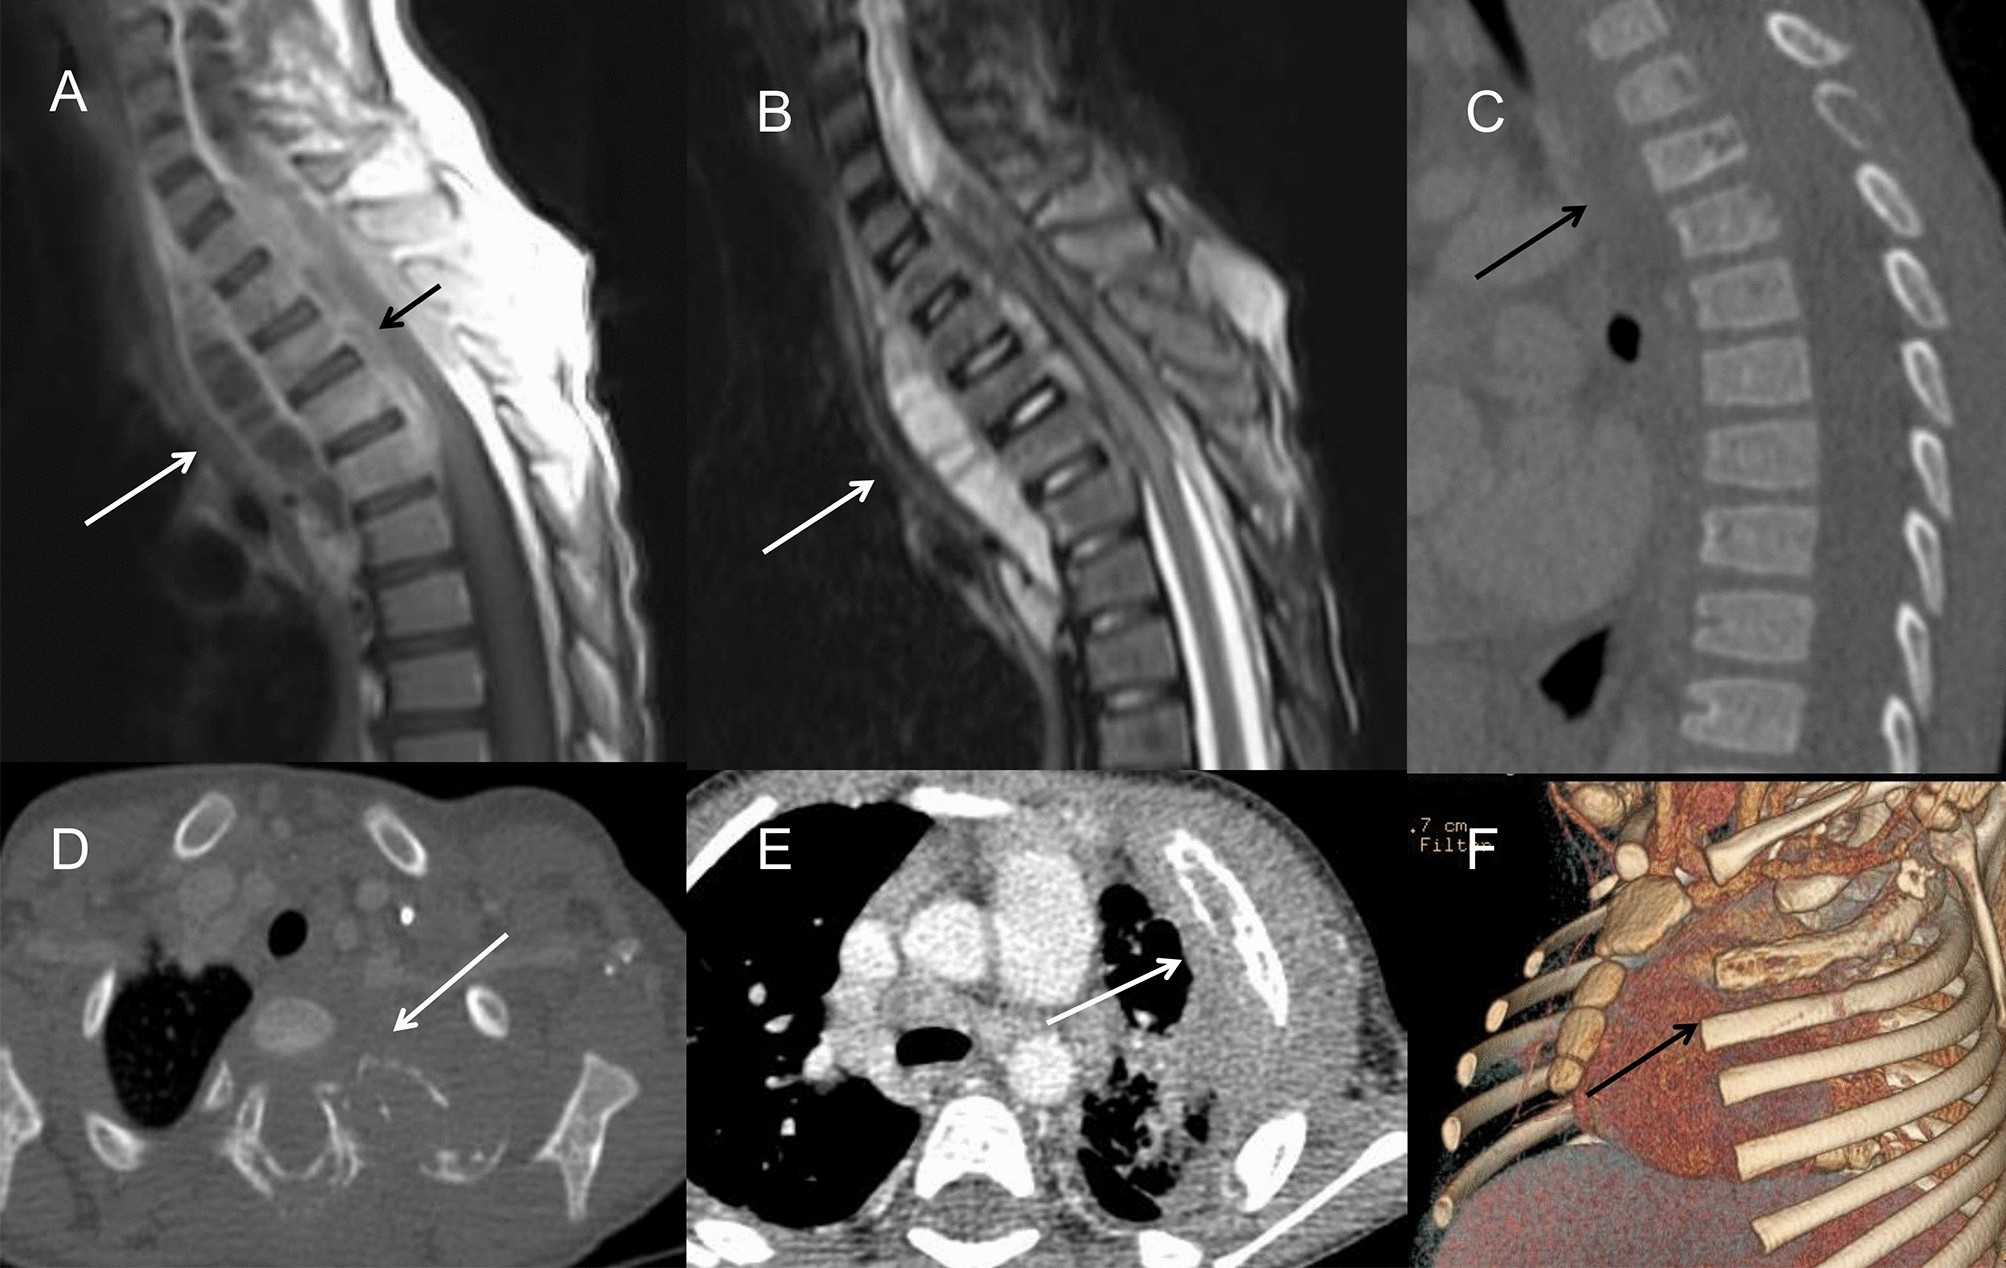

Figure 5

(A–D) A 3-year-old boy with infection of TB. (A) On CT, the 3rd thoracic vertebra was slightly compressed and the 3rd and 4th thoracic vertebra had multiple small areas of osteolysis (long arrow). (B) On T2WI image, paravertebral abscess extending into the spinal canal and compressing the thoracic spinal cord could be found (long arrow). (C) The abscess wall was markedly enhanced on post-contrast T1WI sequence (long arrow). (D) On axial CT image, the osteolysis and expansion of the left first rib and vertebral plate were found (long arrow). (E,F) A 2-year-old boy with fungi infection. On CT images, osteomyelitis of the left 2nd rib and surrounding soft tissue swelling were showed (long arrow). The adjacent lung infection and pleural thickening were also noticed.